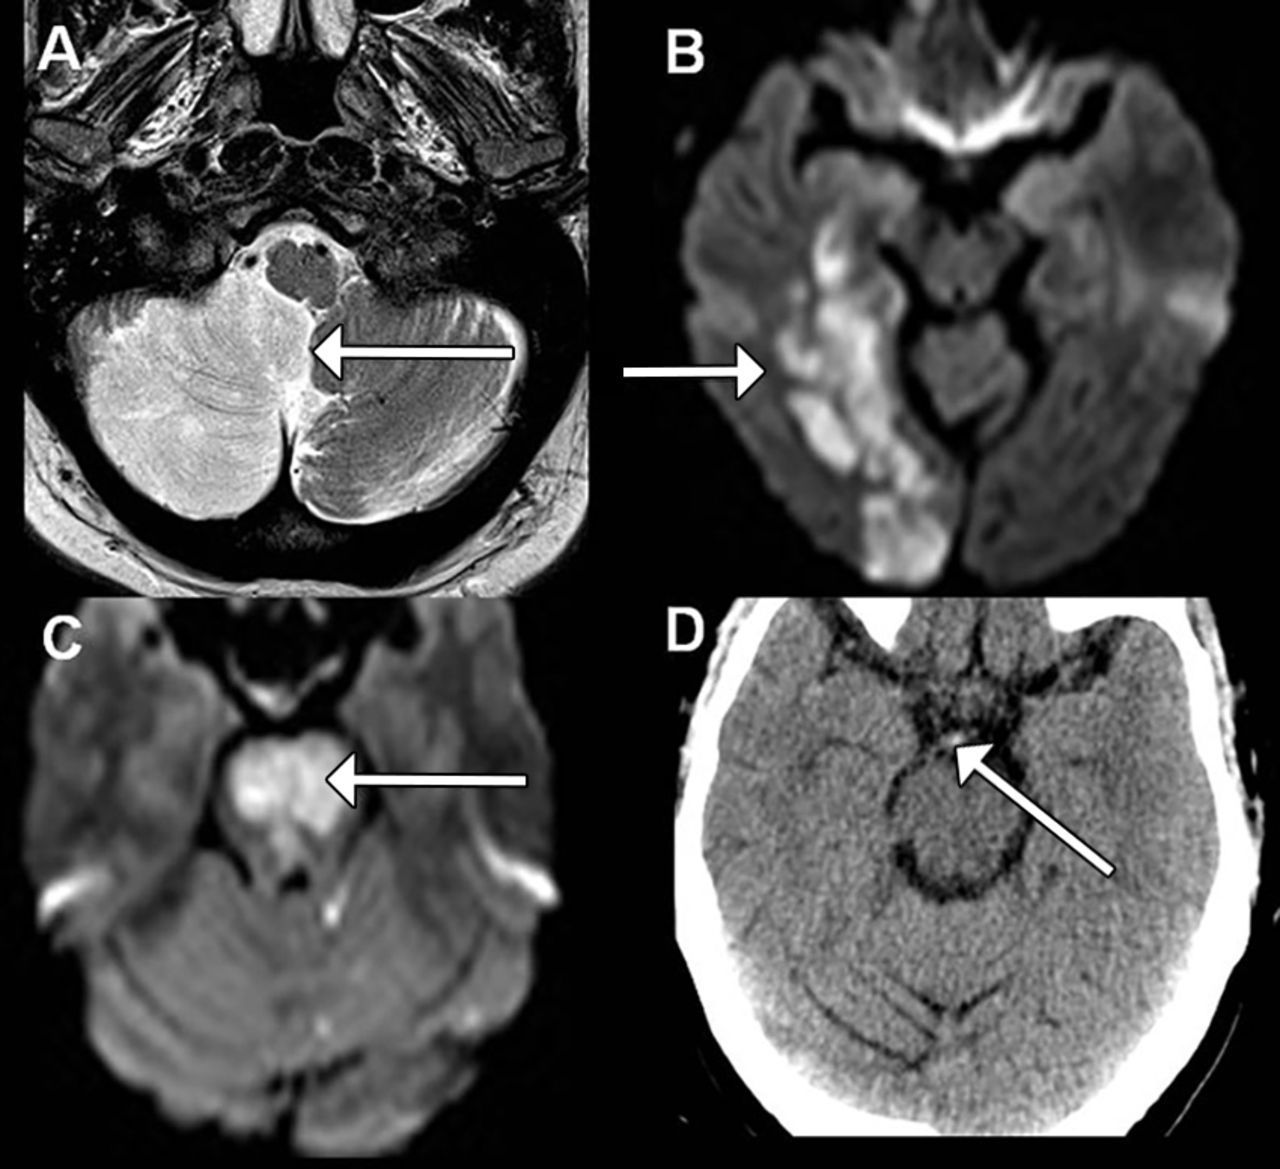

Due to the relatively low prevalence of posterior stroke as compared to anterior stroke, the signs and symptoms can be difficult to identify. The first and foremost step in the diagnosis if a posterior stroke is an increased index of suspicion. The signs and symptoms of posterior stroke can be identified keeping in mind the 5 Ds: 1. Dizziness 2. Diplopia 3. Dysarthria 4. Dysphagia 5. Dystaxia Reference: http://www.emdocs.net/posterior-stroke-hints-exam/ Image via: https://www.bmj.com/content/348/bmj.g3175